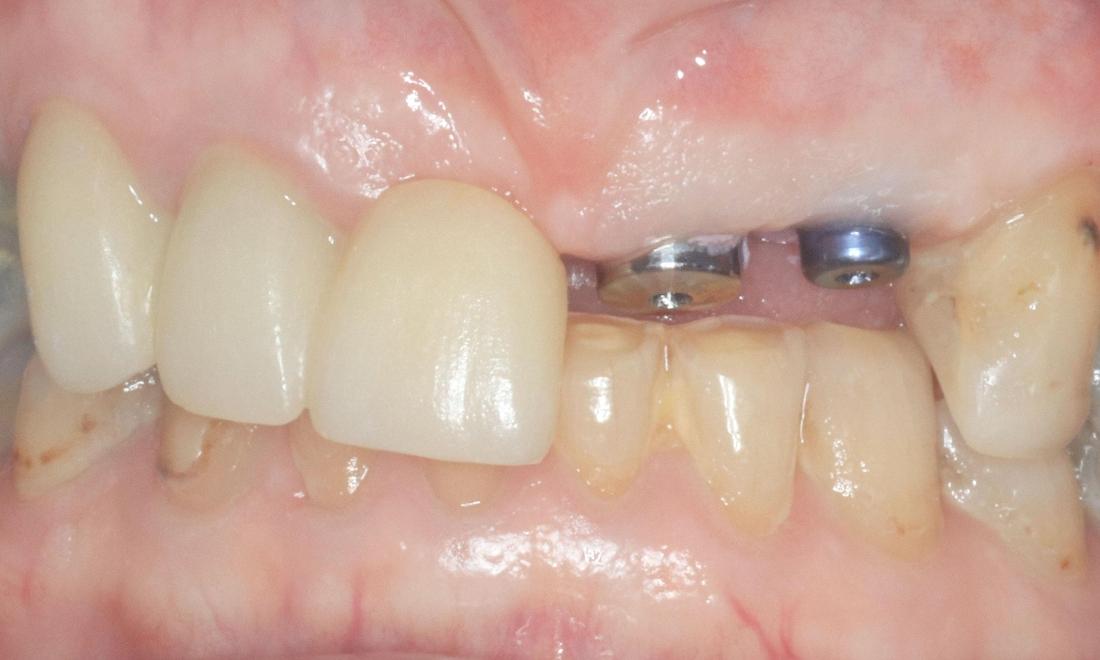

An elderly patient had a dental bridge replacing a missing front tooth for many years. The dental bridge failed as the anchor tooth snapped at gum line resulting in two missing teeth. Two options were discussed i.e. removable denture (plate) or implant-supported teeth.

The patient decided to go with implant-supported teeth. The snapped tooth was removed at the same time placing two dental implants. Three months following dental implant placement, two front teeth were secured individually to dental implants in Armidale, NSW. The total treatment time was 3 months.